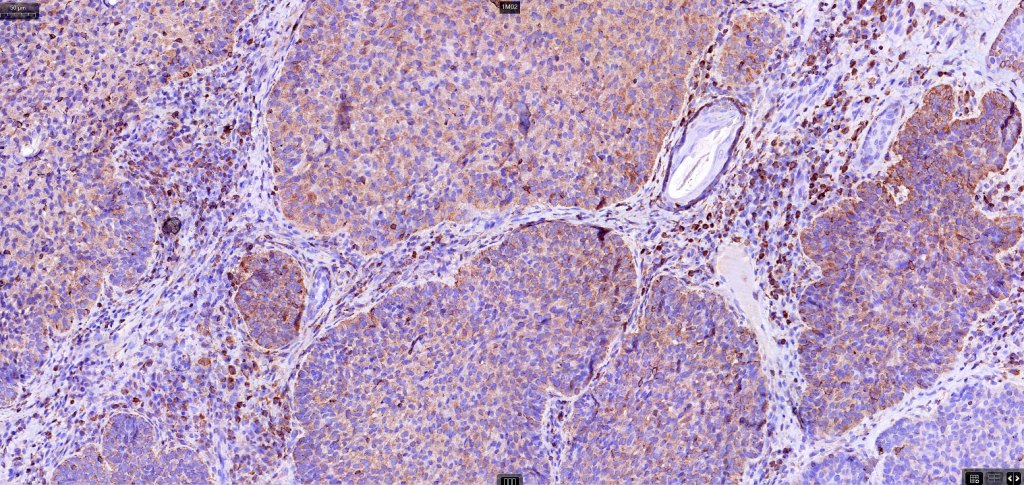

•AE1/AE3, BerEP4, p53, p63, androgen receptor, CD10 (epithelial, negative in stroma)

.EMA, CEA, CD34-ve